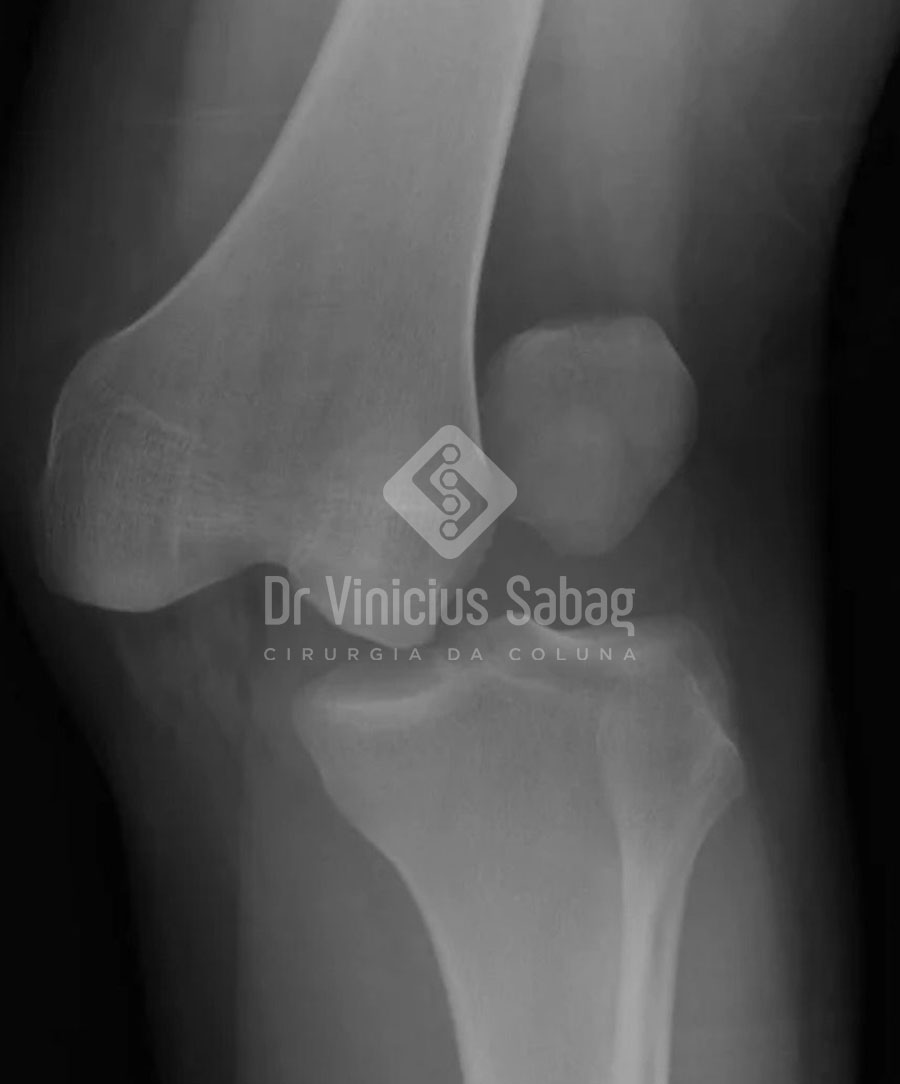

O Que é Luxação?

A luxação ocorre quando uma articulação perde o seu contato articular. Isso acontece quando as estruturas que estabilizam a articulação — como ligamentos e cápsulas articulares — são forçadas além do limite (o famoso ‘saiu do lugar’).

Principais Sintomas da Luxação

- Dor intensa imediata

- Deformidade na articulação

- Inchaço

- Incapacidade de movimentar a articulação

- Sensação de que o osso “saiu do lugar”

A luxação geralmente exige redução da articulação, que é o reposicionamento no lugar correto, realizado por um médico.

Após isso, pode ser necessário:

- Imobilização

- Fisioterapia

- Em alguns casos, cirurgia para estabilizar a articulação afetada